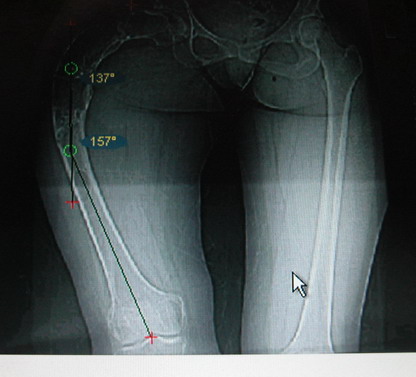

Возможна аппаратная коррекция оси с формированием клиновидного регенерата, которая решила бы и проблему укорочения (что, впрочем, нужно уточнить по схеме, сделанной по рентгенограмме с хорошим захватом смежных суставов - схемка по присланному снимку в приложении). По окончании коррекции - блокируемый стержень, который и сократит время пребывания в аппарате, и вообще возврата к нормальной жизни, а также будет мерой профилактики патологических переломов.

Собственно сустав не беспокоит, объем движений полный. По скиаграммам получается, что достаточно одной остеотомии на вершине деформации, чтобы восстановить длину и вывести коленный сустав в нужное положение.

Т.к. укорочение 7 см, то начинать будем с соеотомии и коррекции аппаратом. Спасибо